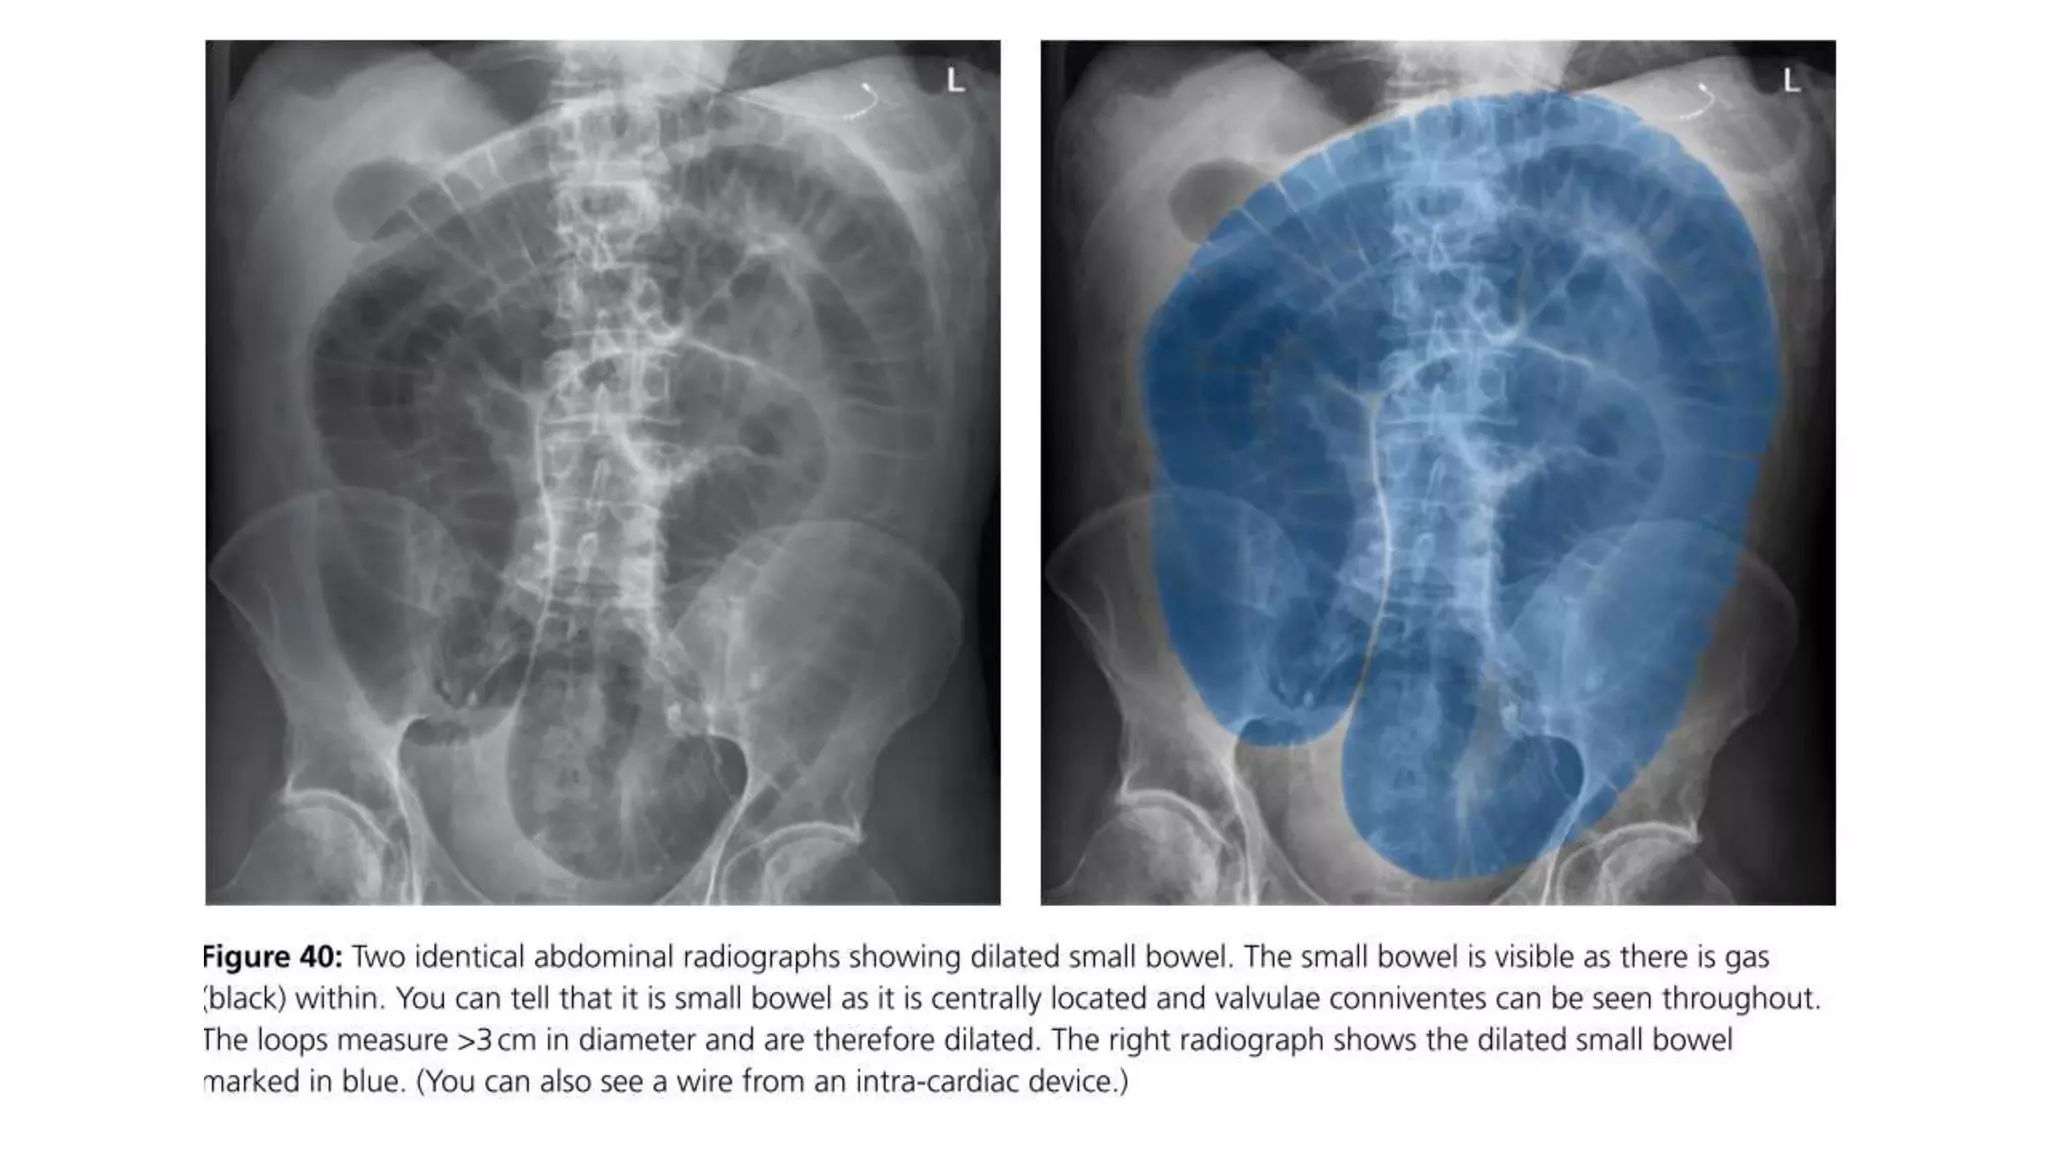

Radiological signs tolook for in SB & LB:

• 43.

Radiological signs tolook for: • Dilation >3 cm: The small bowel is dilated if it measures over 3 cm in diameter. • Central location: The dilated loops are more likely to be centrally located on the abdominal radiograph. • Valvulae conniventes: These are the mucosal folds of the small intestine. They are thin, closely spaced and classically seen as a continuous thin line across the entire width of the bowel. • Air fluid level in upright position